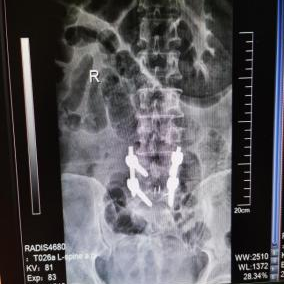

为提升区域内基层医疗机构糖尿病足诊疗服务能力、促进青年医师对糖尿病足的规范化诊治水平,遵义市第二城市医疗集团总院(贵州航天医院)圆满举办贵州省继续医学教育项目——胫骨横向骨搬移技术治疗糖尿病足专题研讨班。 贵州航天医院党委委员、副院长彭亮出席会议并致辞,遵义市第二城市医疗集团各成员单位,以及红花岗区、汇川区、绥阳县、桐梓县等多个区县的基层医疗机构骨干医师参加会议。 研讨班 本次研讨班以胫骨横向骨搬移技术在糖尿病足治疗中的应用为核心主题,围绕糖尿病药物治疗与生活方式管理策略、围手术期血糖精准调控要点、胫骨横向骨搬移技术典型病例深度解析、糖尿病足的临床分型与个体化治疗方案制定等临床实践中的热点与难点展开深入探讨,通过专题授课、案例研讨、互动交流等多元化形式,为参会者搭建了理论与实践结合的学习平台。 此次研讨班不仅为区域内基层医院搭建了学术交流与经验共享的平台,更对推动糖尿病足预防、诊断与治疗的规范化、系统化发展起到了积极作用,有效助力青年医师更新专业知识体系、提升临床技能,为进一步保障区域内糖尿病足患者的健康奠定了坚实基础。 贵州航天医院骨科专家简介 陈明勇 骨一科主任,副主任医师 临床擅长:从事创伤骨科工作约20年,对骨缺损、骨不连、骨肿瘤、肢体畸形等的肢体矫形重建及功能重建,慢性化脓性骨髓炎的根治治疗、糖尿病足的保肢治疗、快速康复理念(ERAS)下的老年骨折的诊治,四肢复杂骨折的诊治,四肢骨折等微创手术治疗具有丰富的临床经验。 2004年毕业于遵义医学院临床专业,曾在中国人民解放军总医院、广西医科大学第一附属医院、上海第六人民医院骨科进修。中国中西医结合学会骨伤科专业委员会横向骨搬移治疗糖尿病足及微血管网再生学组首届委员,遵义市医学会创伤分会常务委员。 瞿 晖 骨科党支部书记,骨二科主任,副主任医师 临床擅长:对骨科的常见病、关节外科、脊柱外科及运动医学疾病的诊治具有丰富的临床经验,熟练掌握骨科手术操作技术。 毕业于遵义医学院临床医学系,2005年前往广州中山大学第一附院骨显微医学部进修学习,2011年前往成都华西医院进修学习,并多次在省内外学习骨科相关知识,是中华医学会骨科分会会员。 赵小锋 中共党员,骨二科副主任,副主任医师 临床擅长:从事骨科临床工作11年,对骨科常见病、多发病诊疗有较为丰富的临床经验,擅长脊柱相关疾病诊断及治疗,尤其是颈、腰、腿疼痛疾病诊断及治疗,擅长胸腰椎骨折微创经皮穿刺内固定术、经皮穿刺椎体成形术、经皮穿刺脊柱内镜下腰椎间盘摘除术、单纯开创腰椎间盘摘除术、腰椎滑脱复位椎间植骨椎融合内固定术、腰椎管狭窄减压融合内固定术及人工髋、膝关节置换术等。 2012年毕业于遵义医学院外科学专业硕士研究生,2019年参加“遵义市115医学人才精英计划”于上海交通大学第一附属医院培训学习,2023年于北京大学第三人民医院脊柱外科进修学习,曾获得遵义市优秀医师荣誉称号。 遵义市手外科第一届委员,遵义市医学会创伤分会第一届委员,遵义市医学会创伤分会第二届委员,贵州省康复医学会第三届脊柱脊髓专业会委员,遵义市医学会烧伤与整形外科学分会委员,发表论文5篇,其中国家级核心期刊1篇,SCI论文1篇,主持市级课题1项并结题,参与市级课题2项。 赵兴东 骨科主任医师 临床擅长:擅长骨科的常见病及各种创伤、四肢骨折创伤修复、骨感染、手足疾病的诊治和手足体表畸形的矫形整复,熟练掌握骨科四肢骨病及创伤的手术操作技术,尤其在四肢关节复杂性损伤、手足外伤、组织缺损创面、难治创面的皮瓣修复方面及平足、高弓足矫形方面及四肢慢性疼痛诊治、康复方面具有丰富的临床经验。 硕士研究生,毕业于遵义医学院临床外科系,2015年前往山东省立医院手足外科进修学习;遵义市医学分会创伤分会第一、二届委员,遵义市手外科医学会第二委届员会常务委员;在省级及省级以上期刊发表文章9篇,参编著作2部,参与主持并完成市级课题1项,参与市级课题2项、省级课题1项。 张艳金 中共党员,骨科副主任医师 临床擅长:从事骨外科工作16年,对复合伤、多发伤的救治、四肢骨干骨折、关节周围骨折、骨肿瘤、骨髓炎等诊治具有丰富的临床经验。 中共党员,硕士研究生,2006年本科毕业于山西医科大学第二临床医学院,2011年研究生毕业于北京军区总医院;在“老年COPD患者合并髋部骨折的诊治”国际合作课题组研究两年,在老年髋部骨折的诊治方面具有丰富的经验,并发表论文6篇;主持遵义市级课题1项,承担遵义医科大学的临床教学工作,获得遵义医科大学优秀带教老师荣誉。编撰有《骨科疾病诊疗精粹》一书,开展2项新技术,编撰地方规范《务川自治县创伤骨科常见疾病诊疗规范》一书。 张俊凯 骨科副主任医师 临床擅长:从事骨科临床工作28年,对创伤骨折、骨感染、骨缺损、骨不连等外科诊治,四肢骨折的微创手术治疗,四肢复杂骨折(如关节内粉碎性骨折、多发骨折等)的损伤控制及手术治疗等具有丰富的临床经验。 1995年毕业于遵义医学院临床专业,2009年前往复旦大学附属医院骨科进修1年。 卢懿明 中共党员,骨科副主任医师 临床擅长:从事骨科工作18年,对创伤骨折、四肢骨折的微创手术治疗、四肢复杂骨折(如关节内粉碎性骨折、多发骨折等)的损伤控制及手术治疗,尤其是髋部骨折的PFNA等微创技术,踝关节骨折、膝关节周围骨折的Mipo微创技术等具有丰富的临床经验,开展了4项新技术,发明6项新型专利技术。 2005年毕业于遵义医学院临床专业,2017年,前往南方医科大学第三附属医院骨科进修半年,回院后运用Mipo技术对骨干骨折及干骺端骨折的治疗技术,同时积极开展骨盆骨折、髋臼骨折腹直肌外侧切口的应用;发表了多篇专业论文,经常参与省内外学术交流会授课,获得医院荣誉称号多个。 邬夏荣 骨科副主任医师 临床擅长:从事骨科工作16年,对四肢复杂骨折、骨肿瘤的诊治,尤其是足踝创伤、慢性踝关节损伤、平足症等诊疗具有丰富的临床经验。 2006年毕业于遵义医科大学临床医学专业,曾在陆军军医大学西南医院进修学习,发表多篇骨科学术论文。 余德怀 中共党员,骨科副主任医师 临床擅长:从事骨科工作10余年,对运动医学、骨关节、脊柱外科常见病、多发病的诊治具有丰富的临床经验。 硕士研究生,2011年毕业于遵义医学院临床医学专业,曾前往遵义医科大学附属医院运动医学专业进修学习;是贵州省医学会运动医学分会青年委员,西部关节镜联盟委员;发表多篇骨科学术论文。 冯 乾 骨科副主任医师 临床擅长:从事骨科工作近20年,熟练掌握骨科多发病及常见病的诊治,尤其对脊柱退变性疾病的诊断及治疗具有丰富的临床经验,主要研究脊柱微创相关治疗方式,能熟练开展椎间孔镜及UBE。 曾前往北京大学第三医院进修学习疼痛及椎间孔镜、首都医科大学友谊医院专业进修脊柱内镜;是贵州省康复医学会第三届脊柱脊髓专业委员会委员;发明专利3项、发表脊柱外科专业论文多篇。 贵州航天医院骨科简介 基本情况 贵州航天医院(原3417医院)骨科组建于1968年,前身是以创伤和断肢(断指)再植闻名于世的上海市第六人民医院骨科,中国断肢(断指)再植的奠基者、中科院院士陈仲伟等专家莅临科室指导医疗和教学,并在70年代开展了贵州省首例断肢(断指)再植手术。组建50余年来,诊治患者已逾百万,挽救了无数的伤病员,成为了保障遵义地区人民群众健康的重要支撑。 经过几代人的不懈努力,今天的骨科,已由创伤骨科发展至骨病、骨肿瘤、骨结核等领域,现有脊柱外科、关节外科、四肢创伤、手足外科四个亚专科,成为了集医疗、教学、科研于一体的综合学科,是贵州省临床重点专科、遵义市临床重点专科、遵义市骨科临床医学中心、遵义市基层骨科专科联盟理事长单位。 科室目前开放床位110张,共有医护人员50余人,副高级以上专家18人,硕士研究生15人。拥有一流骨科医疗设备多台,每年不定期选派优秀技术骨干到全国各大知名医学院校进修、学习、参观、交流,并邀请国内、国外知名专家教授来院进行交流、指导,通过不断引进国内外先进的诊疗技术,科室医疗技术水平稳步提升,为广大人民群众提供了优质的医疗服务。 专科特色 骨一科 (一)骨缺损、骨不连的肢体与功能重建 胫骨横向骨搬移技术治疗糖尿病足: (二)慢性骨髓炎的根治治疗 (三)肢体缺血性疾病如糖尿病足、脉管炎的保肢治疗 (四)皮瓣修复 (五)复杂创伤的治疗 (六)老年髋部骨折及小儿骨折快速手术 老年髋部骨折: 骨二科 (一)胸腰椎骨折微创经皮椎弓根螺钉固定术 (二)老年性骨质疏松性患者腰椎滑脱脊柱内固定术(骨水泥螺钉) (三)V形双通道脊柱内镜技术(VBE)腰椎融合术治疗腰椎退行性疾病 (四)老年性骨质疏松性骨折(PVP/PKP)术 (五)人工髋关节置换术 (六)双侧股骨头坏死人工全髋关节置换 (七)右侧全髋置换术后假体周围骨折翻修 (八)人工膝关节置换术 (九)人工膝关节假体松动翻修 (十)关节镜技术 传统手术切口 关节镜技术切口 诊疗范围 骨一科 1.四肢创伤、矫形。 2.手、足踝外科。 骨二科 End